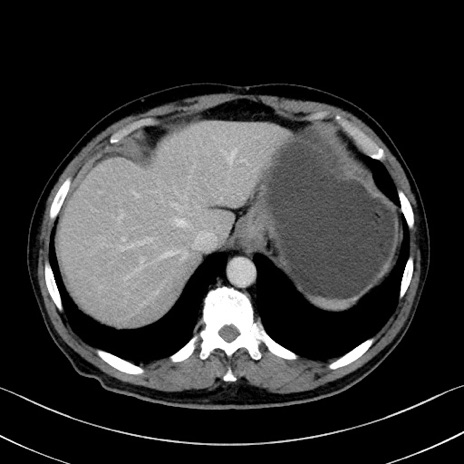

症例35(横断像)

【症例】70歳代 男性

【主訴】腹部膨満、嘔吐

【現病歴】昨日より腹部膨満感出現。本日増悪し、仙痛出現。嘔吐あり、受診。

【既往歴】糖尿病、胆摘後

【身体所見】BP 149/80mmHg、HR 74/min、BT 35.9℃、腹部:膨満、軟、圧痛なし。腸雑音減弱あり。上腹部正中切開瘢痕あり。

【データ】WBC 13500、CRP 1.72